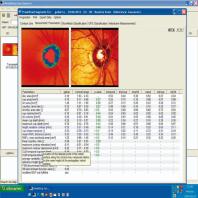

- eFig. 9-3 - Relevé d'écran d'accueil HRT